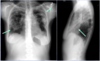

What are the two arrows pointing at? What does the "^" indicate?

* ETT * Central Line

What does this CXR show?

* Right mainstem intubation

Is this a proper placement of a central line?

* No, the tip (smaller red arrow) is within the right ventricle. Pt will probably experience PVCs. * The catheter tip should lie between the most proximal venous valves of the subclavian or jugular veins and the right atrium.